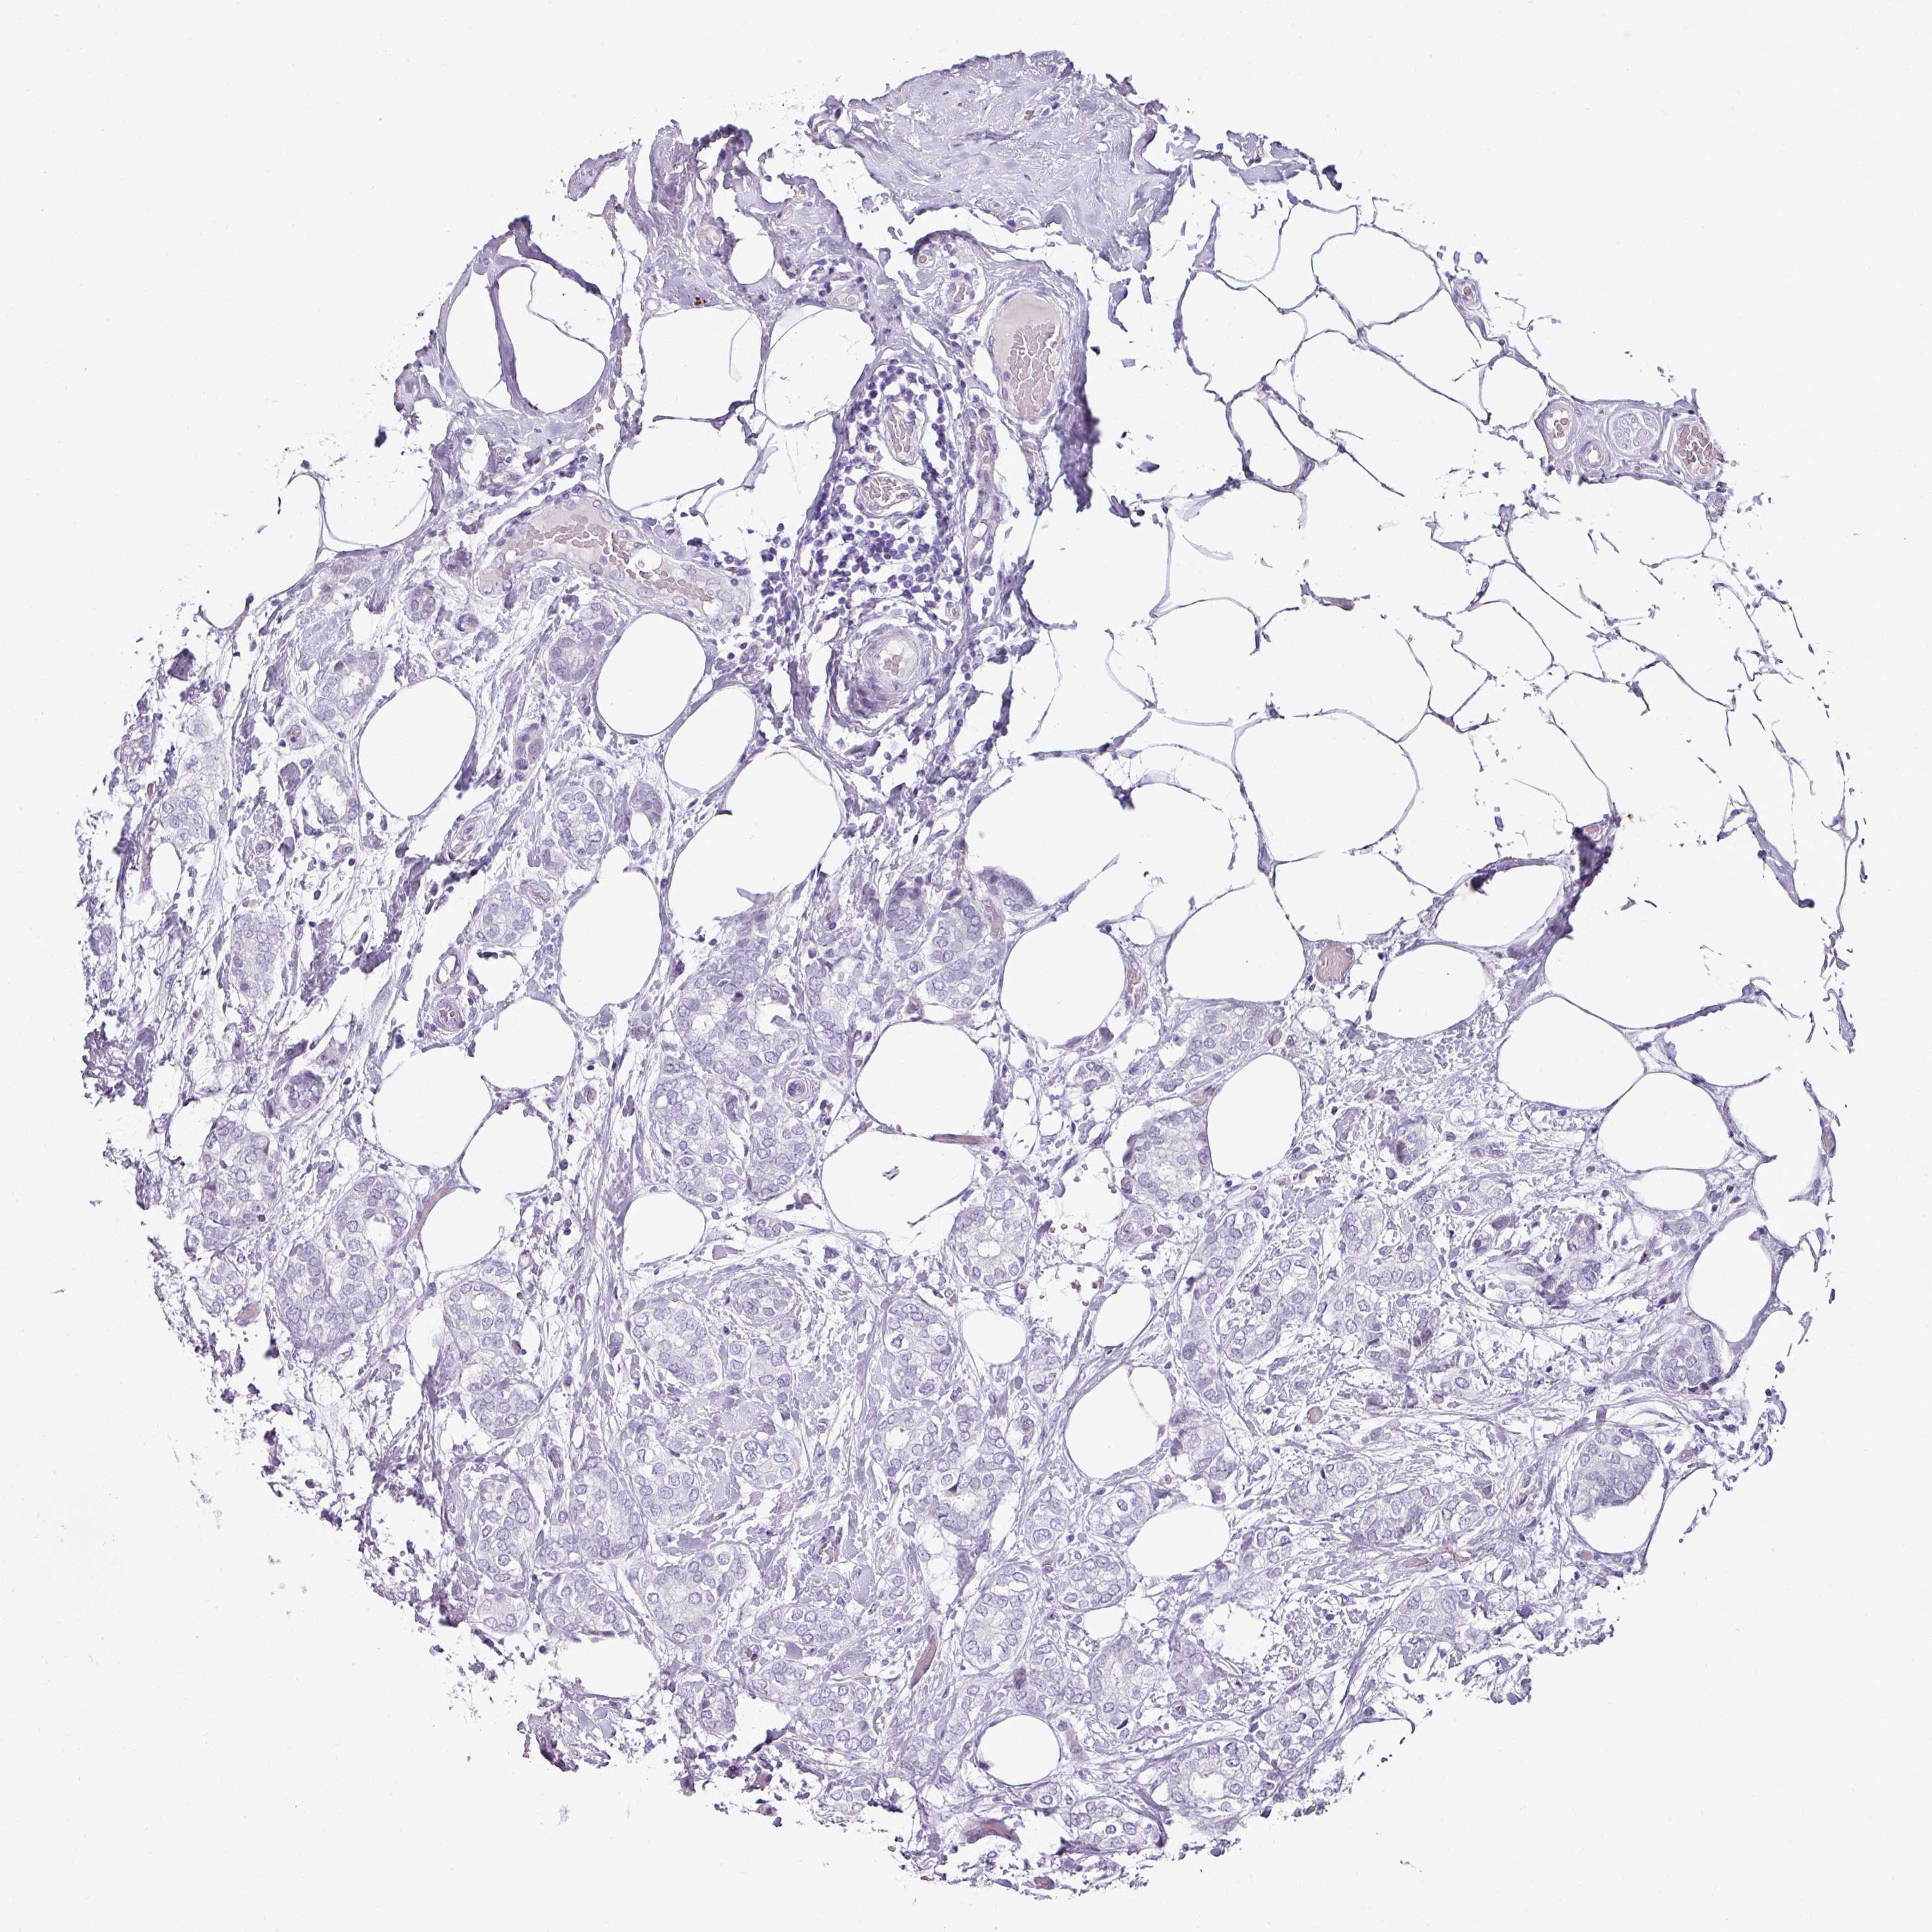

CANCER BREAST CANCER Show tissue menu

BRCA TCGA BRCA VALIDATION PROTEIN EXPRESSION